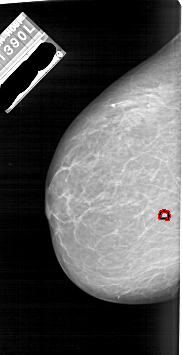

A_1866_1.LEFT_CC

LEFT_CC LINES 6376 PIXELS_PER_LINE 3271 BITS_PER_PIXEL 12 RESOLUTION 43.5 OVERLAY

FILE: A_1866_1.LEFT_CC.OVERLAY

TOTAL_ABNORMALITIES 1

ABNORMALITY 1

LESION_TYPE CALCIFICATION TYPE PLEOMORPHIC DISTRIBUTION CLUSTERED

ASSESSMENT 4

SUBTLETY 4

PATHOLOGY BENIGN

TOTAL_OUTLINES 1

BOUNDARY